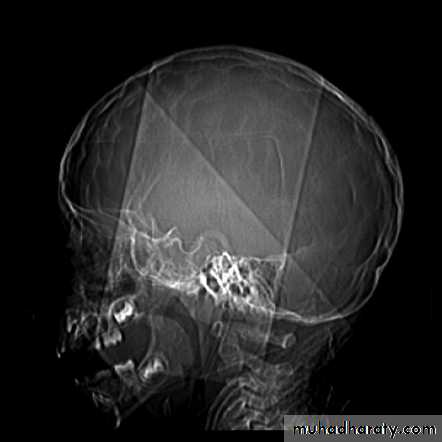

Skull X-ray findings in increased intracranial pressure

• Sutural separation in children.• ‘Copper-beating’ marking of the cranial vault.

• Thinning of dorsum sellae.

• Erosion of the posterior clinoid process.

Copper-beating’ marking